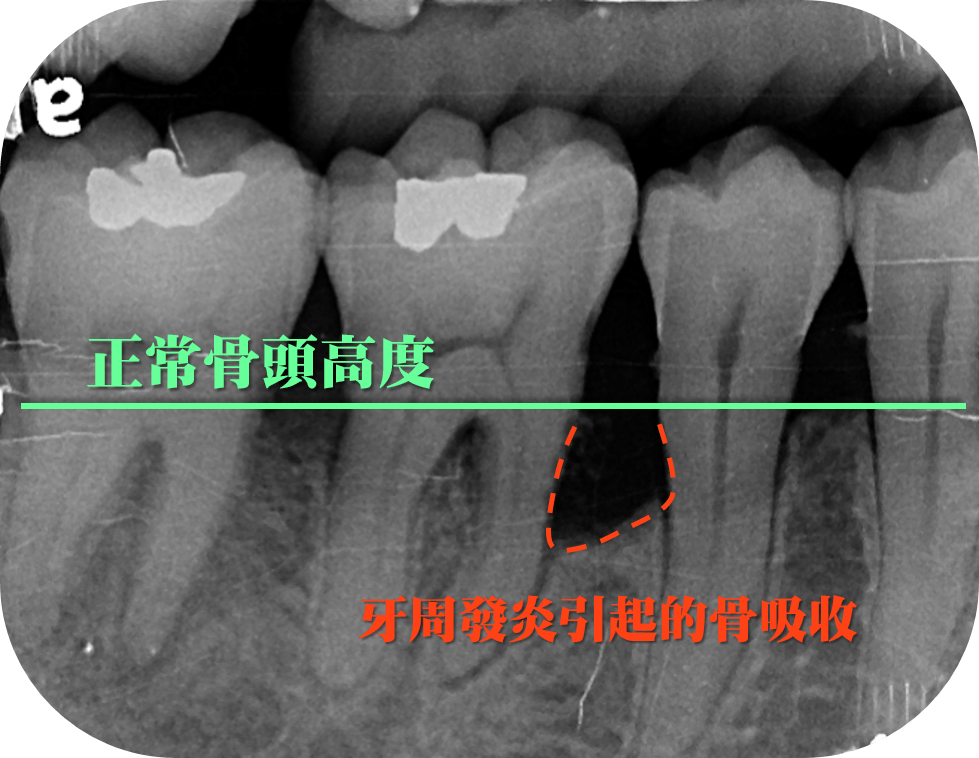

拍攝X光片

許多患者會詢問:「為什麼治療牙周病要拍 X 光片?」

因為透過拍攝 X 光片,才有辦法了解齒槽骨的破壞程度,這是肉眼無法看到的。在 X 光片上,可以明顯的看出牙周發炎引起的骨吸收,齒槽骨的壞破情形。

X光片可以看到牙周發炎引起的骨吸收